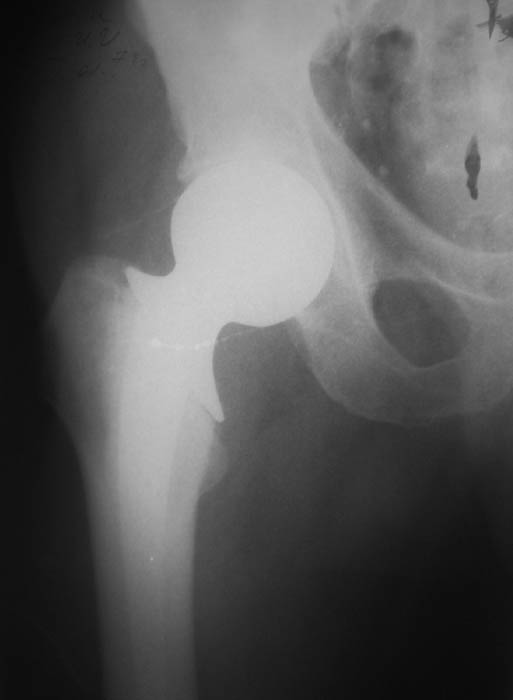

протрузия эндопротеза

Мужчина, 77 лет. В 2000 г. по поводу субкапитального перелома шейки бедренной кости произведена операция эндопротезирования головки. На последних рентгенограммах обнаружена протрузия головки эндопротеза.

В настоящее ведет активный образ жизни, продолжает работать.Предполагается замена протеза на тотальный ревизионный. Интересуют предложения по восстановлению костной массы вертлужной впадины.Заранее благодарю!С уважением,А.В.ВладзимирскийДонецкий НИИ травматологии и ортопедииДонецк, Украина